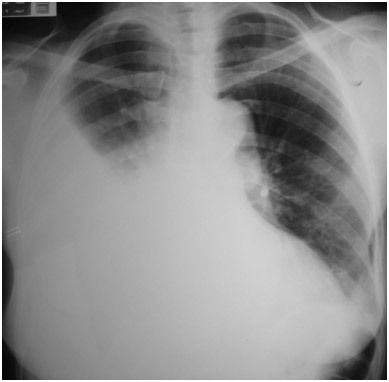

Paciente vítima de trauma torácico com clinica de MV diminuidos ou abolidos, macicez a percussão e jugular colabada, evoluindo com choque hipovolêmico…

Diagnóstico, conduta…

HEMOTÓRAX

Sangramento de vasos intercostais ou parênquima (geralmente auto-limitado)

Conduta: Toracostomia (drenagem em selo d’água)

Avaliar débito de sangue

Quando indicar toracotomia no hemotórax?

Se hemotórax maciço

- Drenagem imediata de > 1500 ml de sangue

- Drenagem constante de > 200-300 ml em 2-4h

- Necessidade persistente de transfusão